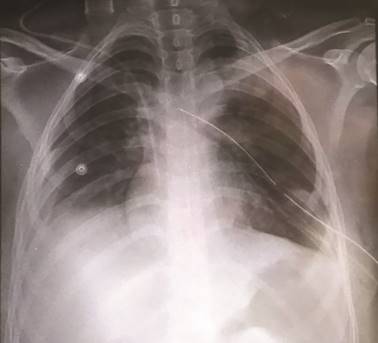

El servicio de radiología observó en el Scout imágenes compatibles con asas intestinales dilatadas con niveles hidroaéreos, los cuales presentaban migración hacia el hemitórax izquierdo con desplazamiento del mediastino a la derecha, con presencia de sonda endopleural sin datos que sugieran perforación intestinal en ese momento (figura 2).

Figura 2 Scout. Ausencia de expansión pulmonar a pesar de la colocación de sonda endopleural. No hay datos de perforación de víscera hueca.

La radiografía de tórax sigue siendo un estudio inicial que aporta información básica para poder realizar el diagnóstico diferencial de un neumotórax, el cual se caracteriza por el aumento de la radiolucidez periférica (dependiente del volumen), visualización de los bordes de la pleura visceral que se dibuja como una línea radiopaca fina, y recordar que el desplazamiento del mediastino solo está presente en el neumotórax a tensión. En la radiografía de la paciente se presentó el desplazamiento del mediastino, ocasionado por el efecto de masa de las estructuras intraabdominales; además de que se alcanzan a delimitar imágenes compatibles con asas intestinales con niveles hidroaéreos que se confirman el corte sagital del Scout.